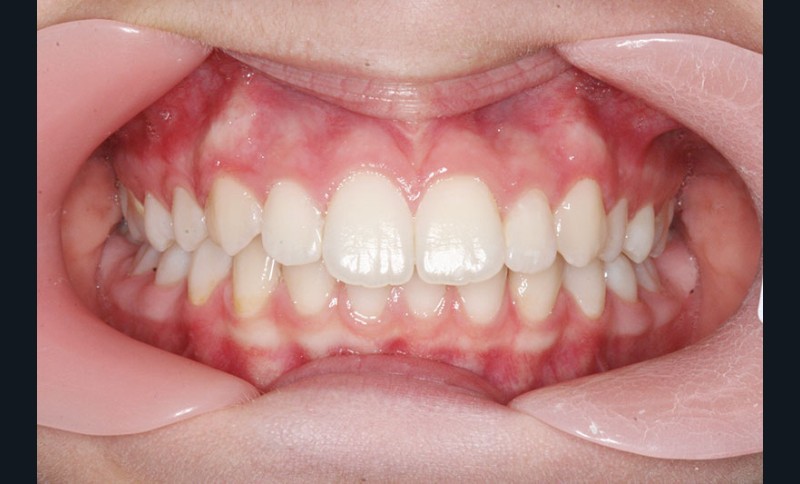

Nous sommes en présence d’une patiente adolescente âgée de 12 ans ½ dans une phase de croissance faciale favorable.

Elle présente une classe II squelettique par rétrognathie mandibulaire et une classe II dentaire molaire et canine droite et gauche associée à une biproalvéolie incisive maxillaire et mandibulaire.

L’environnement vertical est normodivergent.

Le pronostic de correction de la classe II est favorable mais il est très important de souligner la vestibuloversion incisive mandibulaire et le risque parodontal associé (fig. 1 à 3).